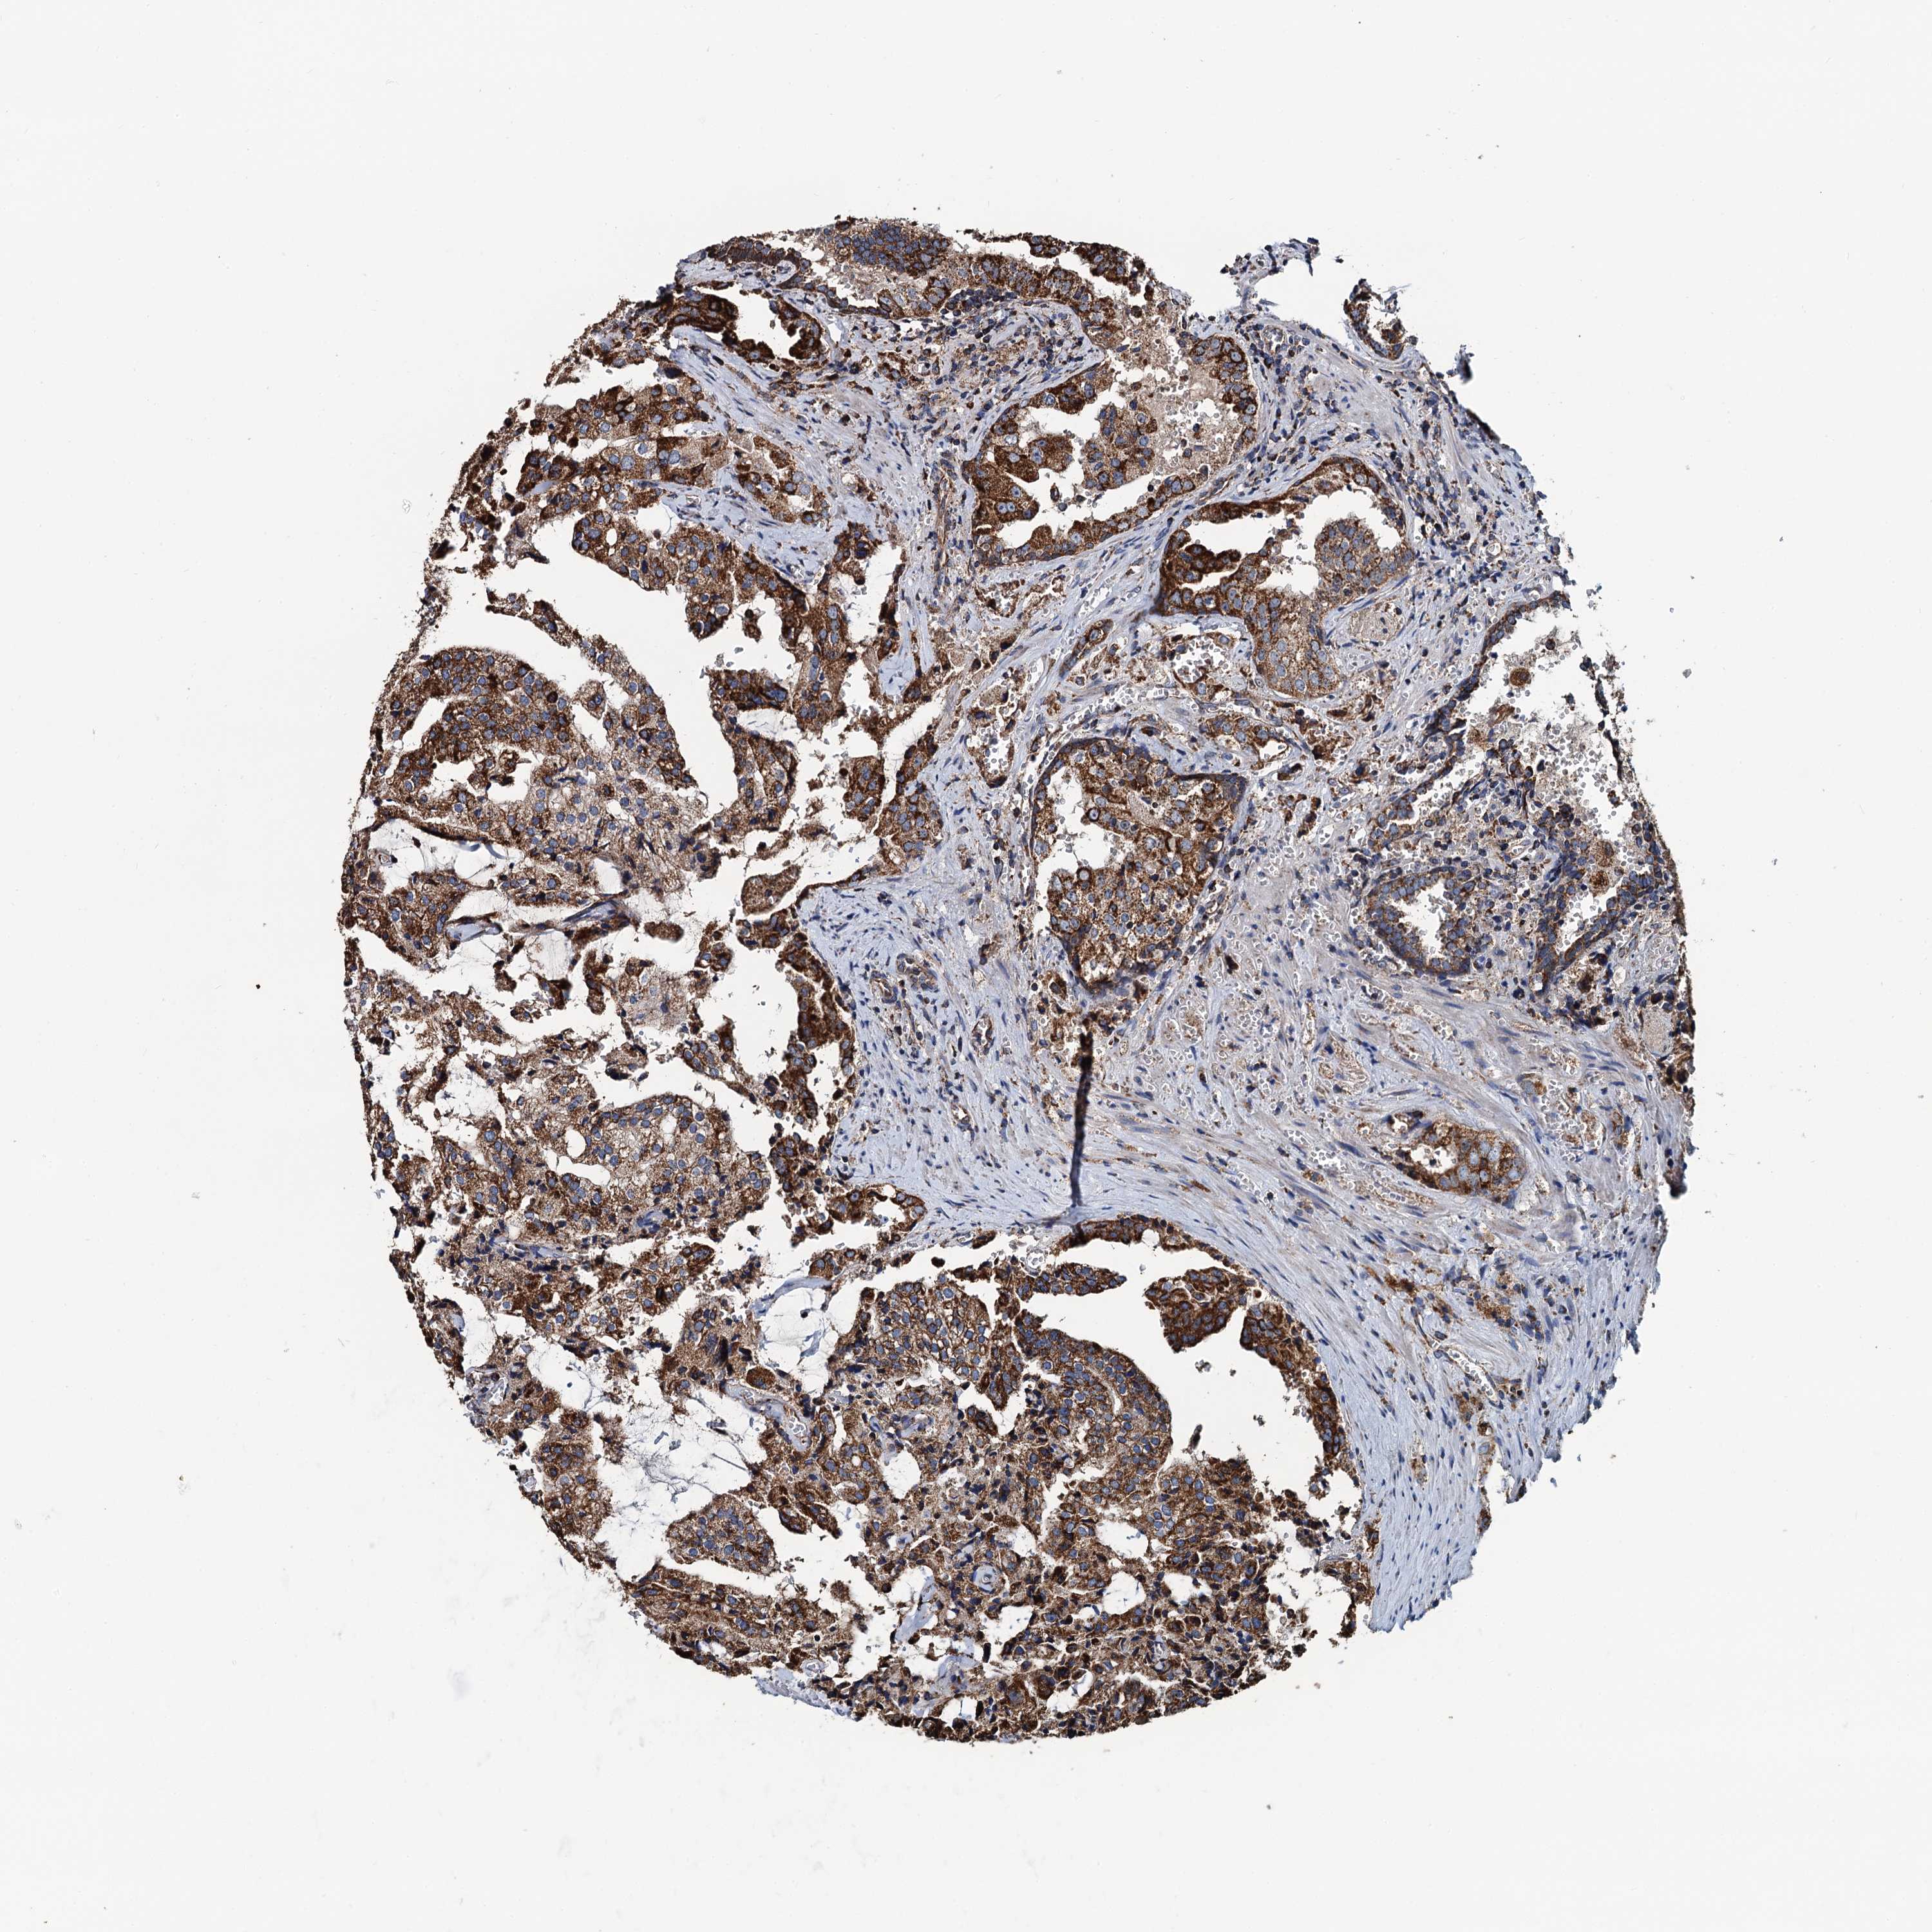

PROSTATE CANCER - Protein expressioni

A mouse-over function shows sample information and annotation data. Click on an image to view it in a full screen mode. Samples can be filtered based on level of antibody staining by selecting one or several of the following categories: high, medium, low and not detected. The assay and annotation is described here.

Antibody stainingi

Antibody staining in the annotated cell types in the current human tissue is reported as not detected, low, medium, or high, based on conventional immunohistochemistry profiling in selected tissues. This score is based on the combination of the staining intensity and fraction of stained cells.

Each image is clickable and will lead to virtual microscopy that enables deeper exploration of all samples and also displays staining intensity scores, fraction scores and subcellular localization as well as patient and tissue information for each sample.

Antibody HPA039371

Antibody HPA040174

Staining

High

Medium

Low

Not detected

Intensity

Strong

Moderate

Weak

Negative

Quantity

>75%

75%-25%

<25%

None

Location

Nuclear

Cytoplasmic/membranous

Cytoplasmic/membranous,nuclear

Adenocarcinoma, NOS

Adenocarcinoma, High grade

Adenocarcinoma, Low grade